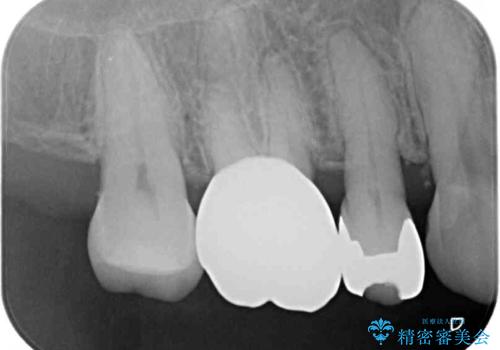

一部歯肉の中にまで虫歯が波及しており、汚れが溜まりやすくなっていましたが、クラウン装着後は汚れが溜まることはなくなりました。

しみていた症状もなくなり、患者様には大変満足していただきました。